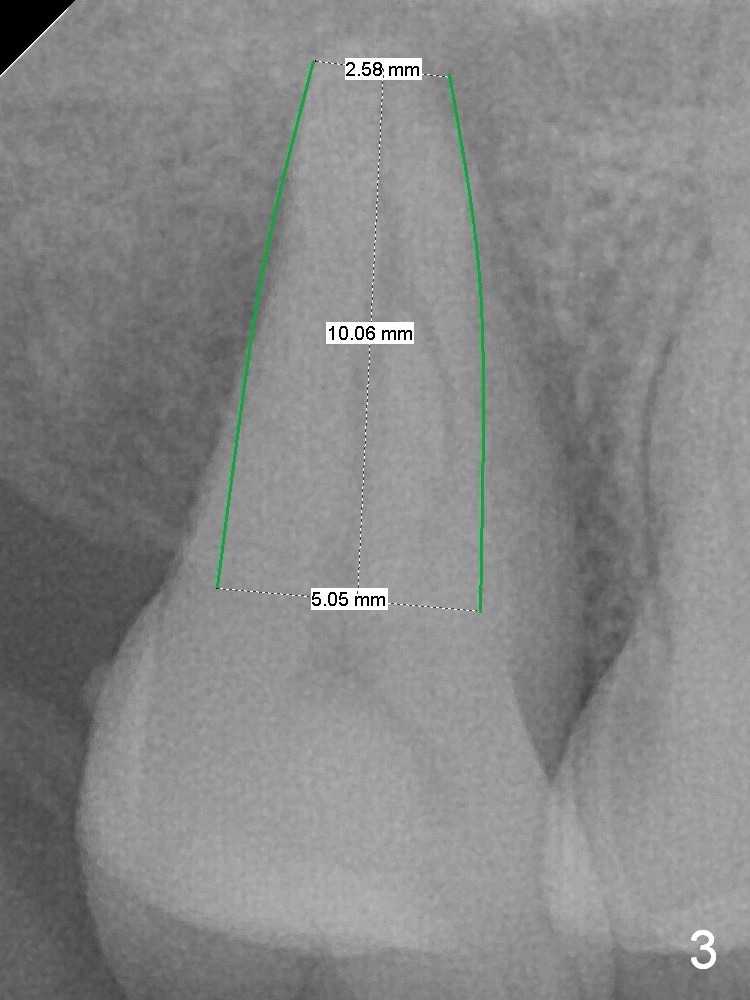

Implant Is Inserted into Socket for Stability

A 53-year-old man agrees implant treatment for crack tooth #2 (Fig.1). Since the apex overlaps the sinus floor (Fig.2 panoramic X-ray), the primary stability will be derived from tight contact of an implant with the socket. After extraction (Metronidazole), osteotomes are going to be used to break through the sinus floor (RT2-4), followed by tap drills (4.5 mm or larger (Fig.3) until achieving 35 Ncm). The implant will be one size larger. Prepare regular and extra wide surgical kits. Before implant placement, insert PRF plug and allograft/Osteogen.